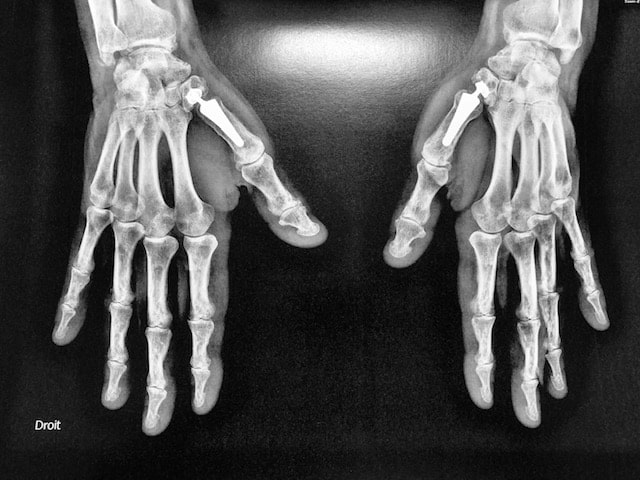

Les fractures ouvertes, ou déplacées avec troubles de rotation seront traitées chirurgicalement. Le choix du traitement chirurgical est fonction de l’os atteint, du siège et du type de fracture.

Schématiquement, la stabilisation après réduction de la fracture est faite soit par broche soit par plaque. Cette chirurgie réalisée en ambulatoire sous anesthésie du bras, doit permettre une rééducation précoce afin de restaurer la fonction de la main. Des pansements sont à faire réaliser par infirmière durant deux à trois semaines. La rééducation sera donc précoce afin de limiter la raideur.

Brochage fracture